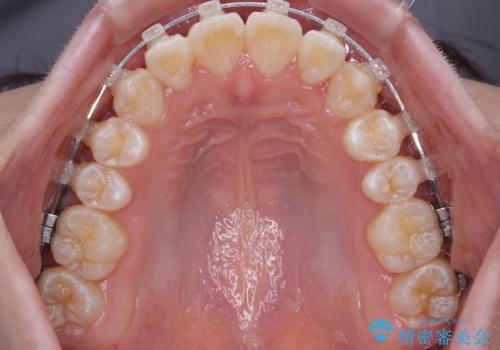

- クリアブラケット

目立ちにくさと費用のバランスを考慮し、プラスチックブラケット+メタルワイヤーを採用。日常生活でも装置の存在感を気にせずお過ごしいただけます。

患者様の協力もあり、およそ1年間で治療を完了。スムーズな歯の移動を実現しました。